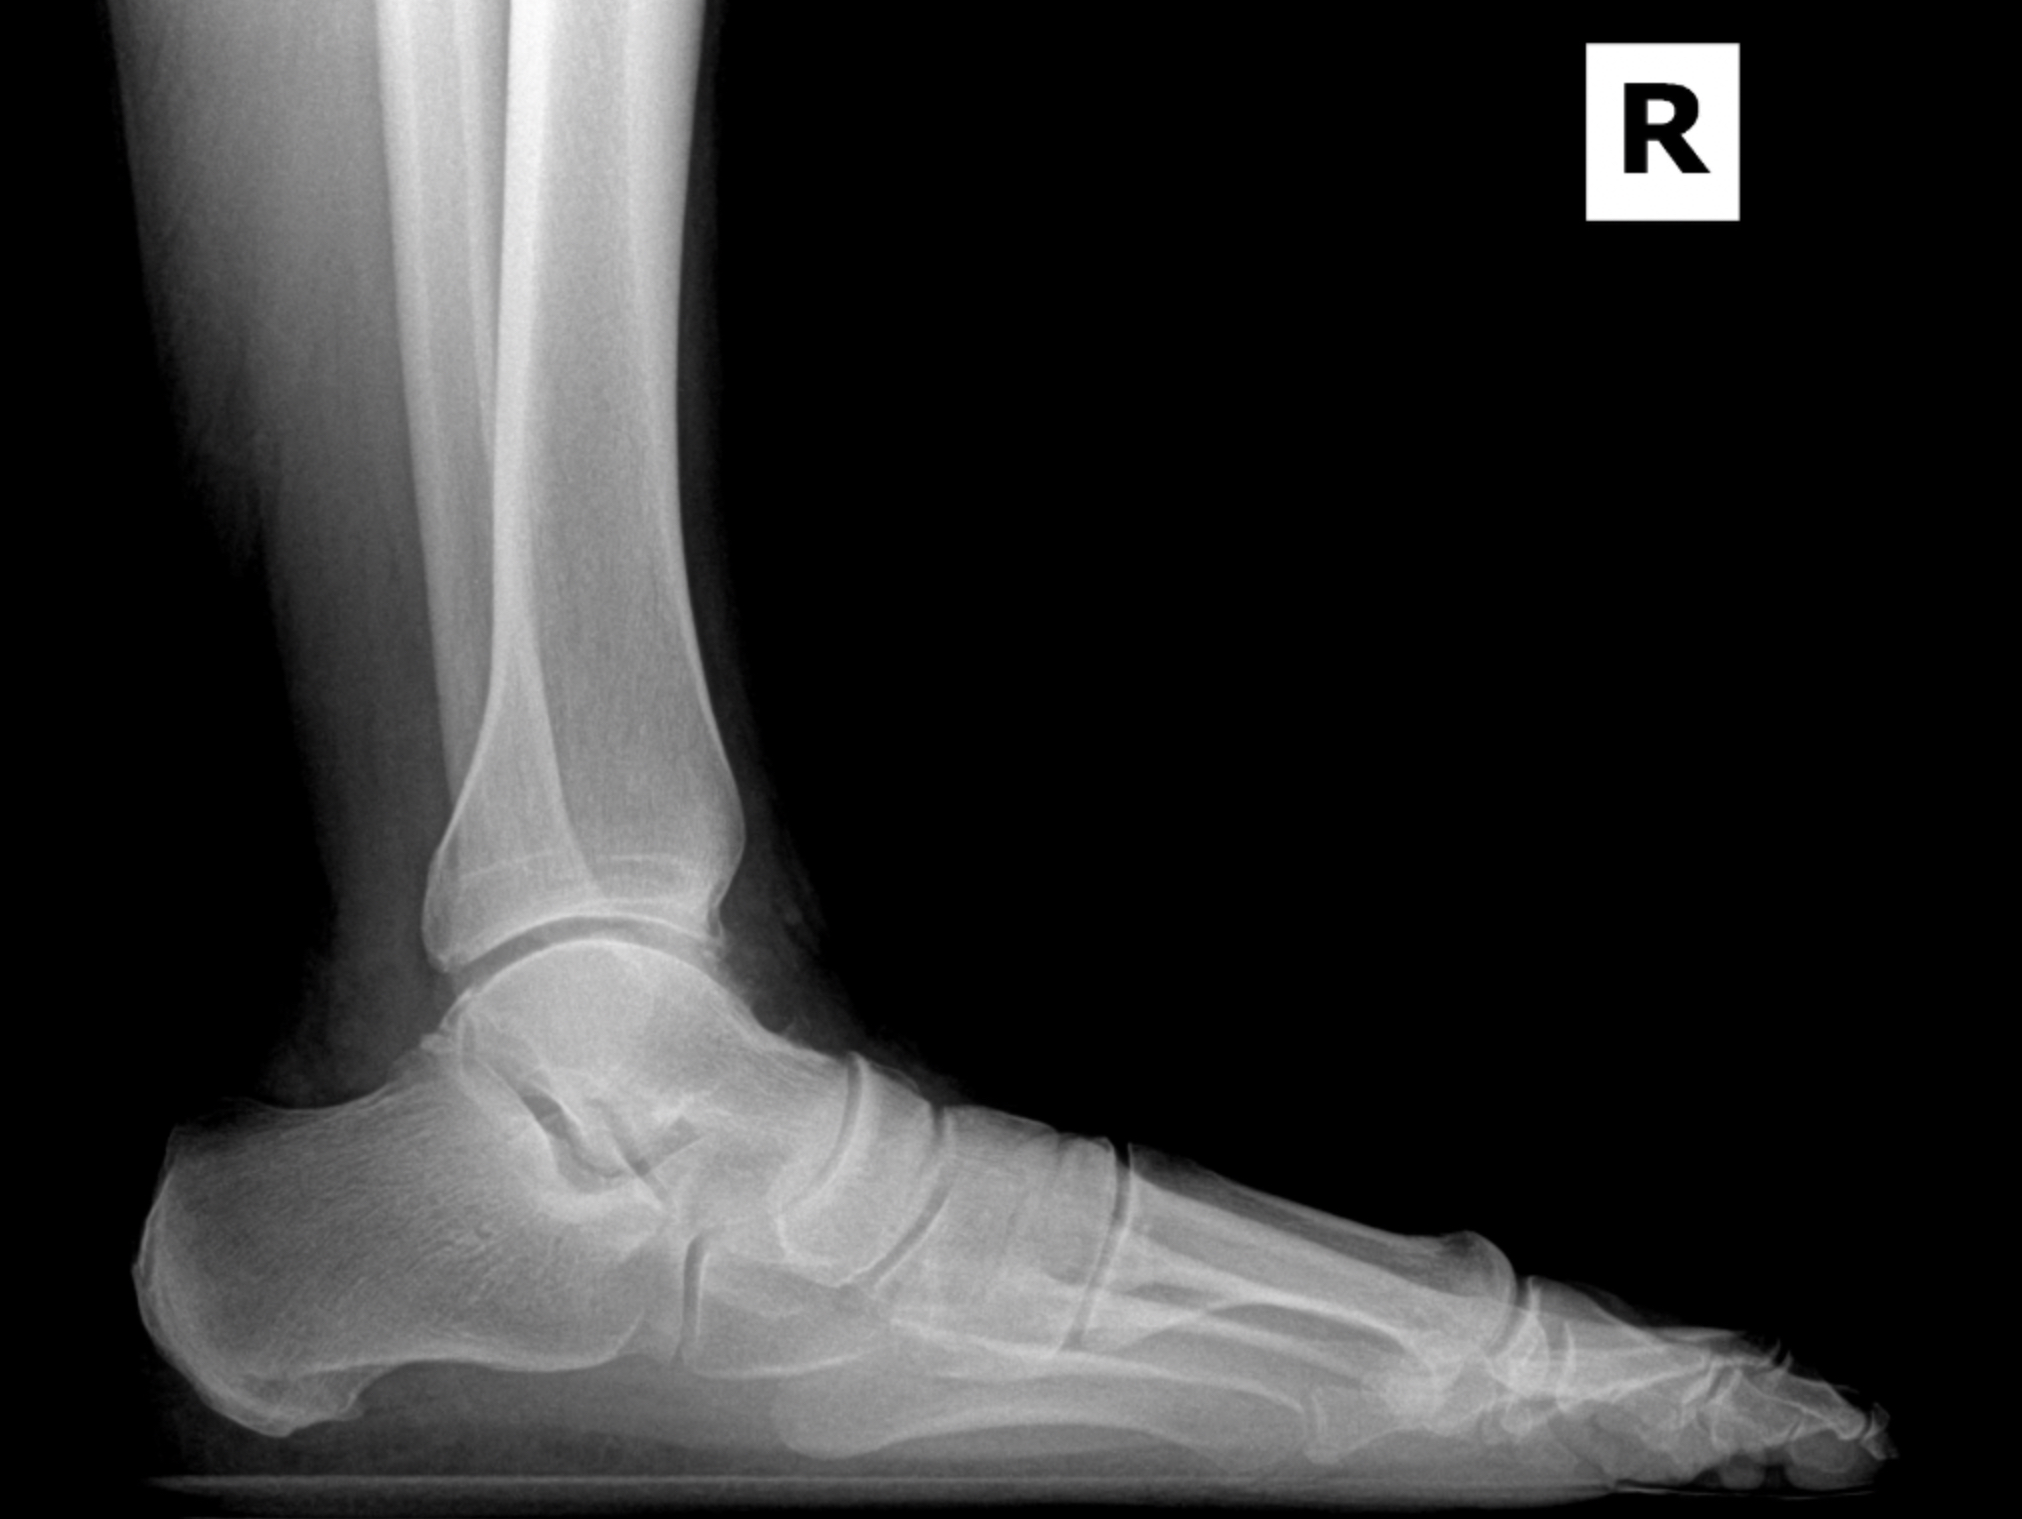

Arthritic flatfoot

Pre-op XR Images